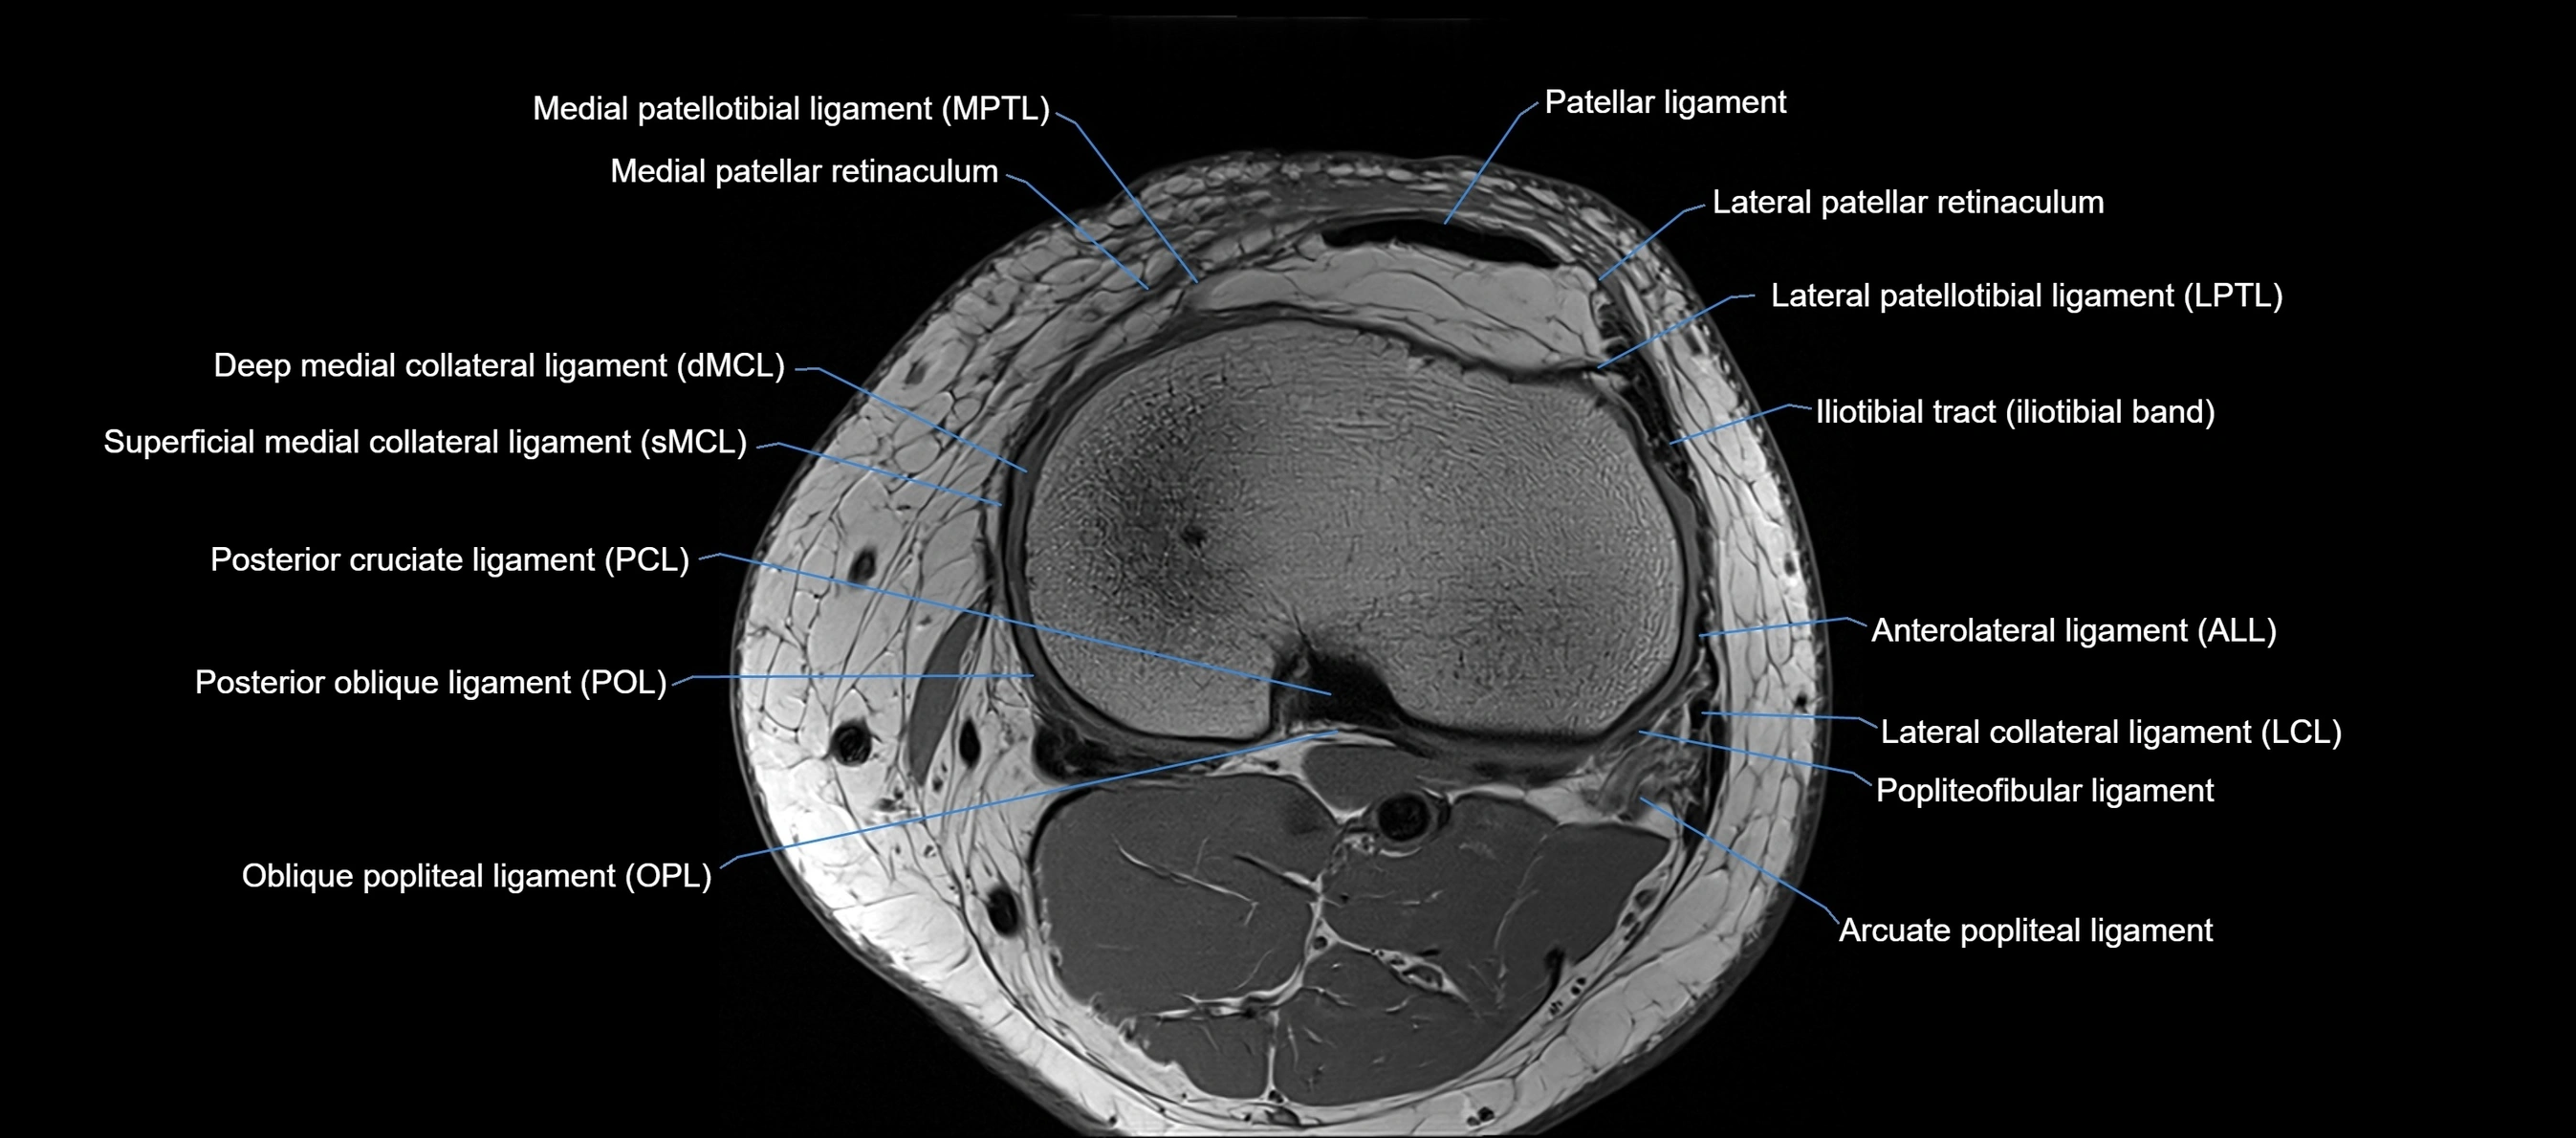

MRI Appearance

T1-weighted images:

• Normal ACL appears as a low-signal band-like structure crossing the intercondylar notch

• Surrounded by intermediate signal synovial fluid and fat planes

T2-weighted images:

• Normal ACL remains low signal

• Partial or complete tears appear as discontinuity, increased signal, or fiber laxity

STIR (Short Tau Inversion Recovery):

• Normal ACL shows dark low signal

• Acute injury shows bright hyperintensity due to edema and hemorrhage

Proton Density Fat-Saturated (PD FS):

• Normal ACL: dark, low-signal band

• Tears: bright intraligamentous hyperintensity, discontinuity, or abnormal course